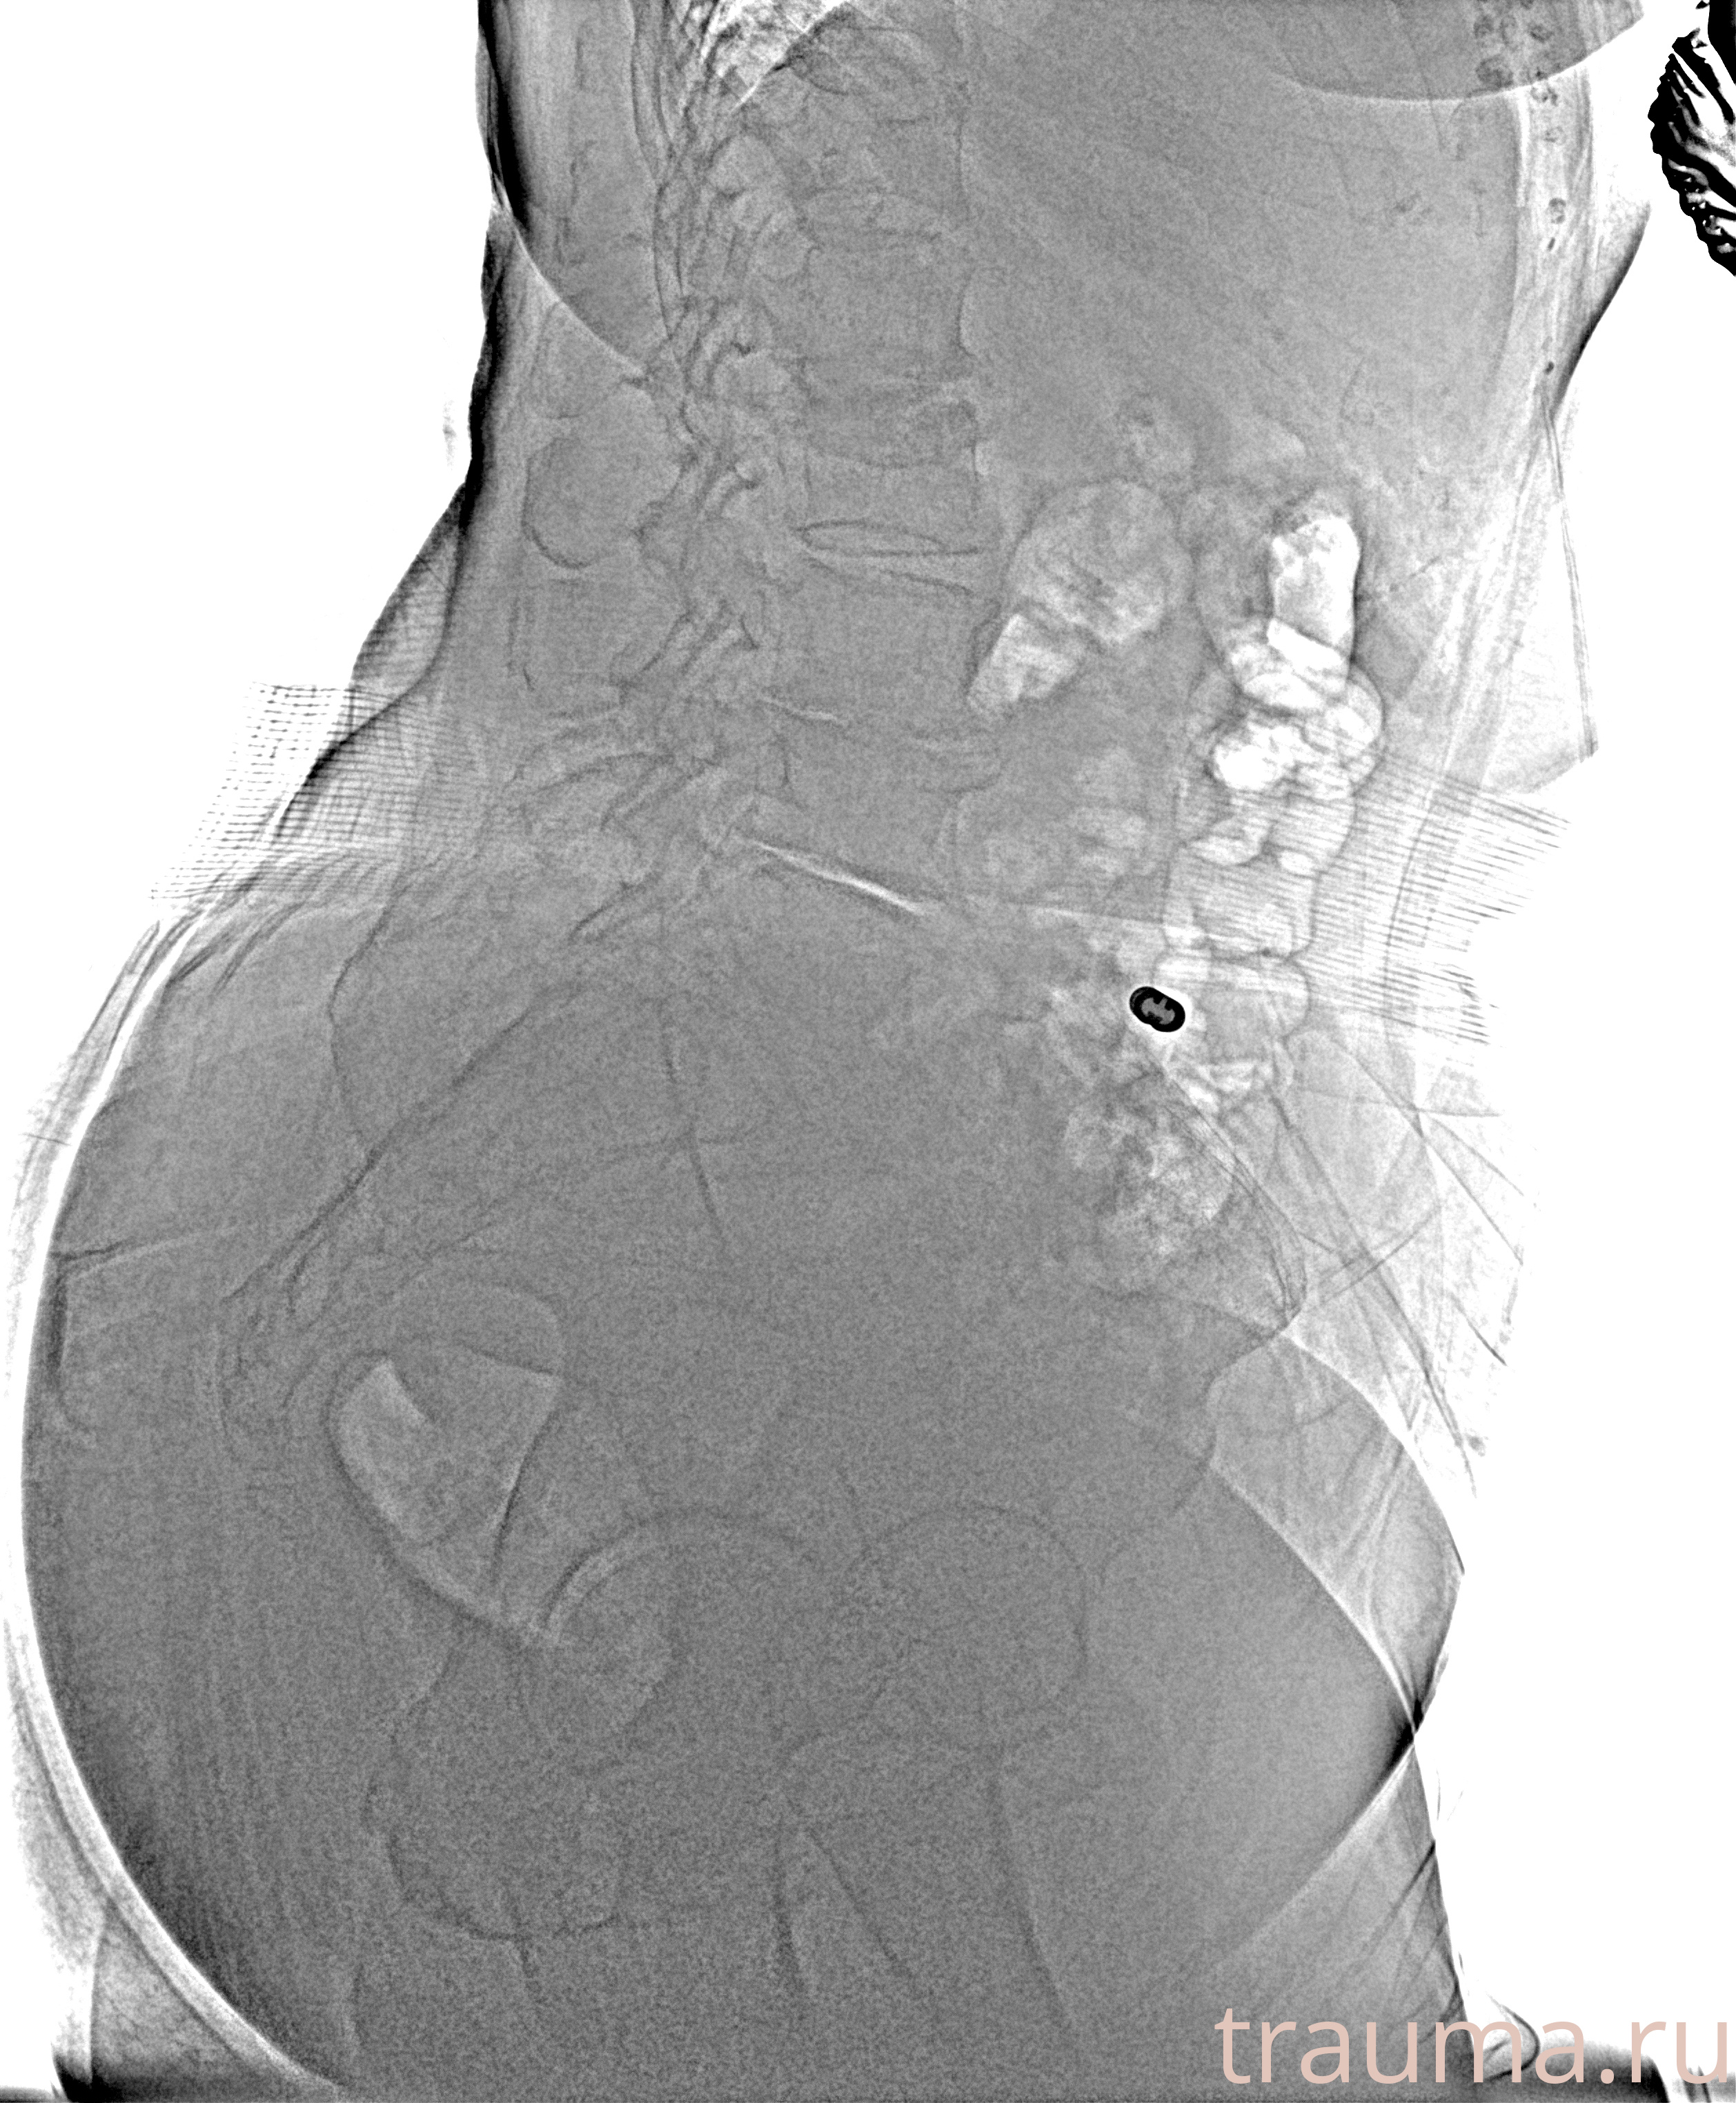

Рентген на дому: по вашему адресу приезжает врач-рентгенолог, травматолог-ортопед с мобильным рентгеновским аппаратом, проводит диагностику травмы или заболевания, делает необходимые рентгенограммы, дает рекомендации по дальнейшему лечению. Получить качественные снимки в домашних условиях возможно благодаря уникальной методике, разработанной МосРентген Центром для института  Склифосовского

при переломе шейки бедра и пневмонии от компании МосРентген Центр - партнера Института имени Склифосовского